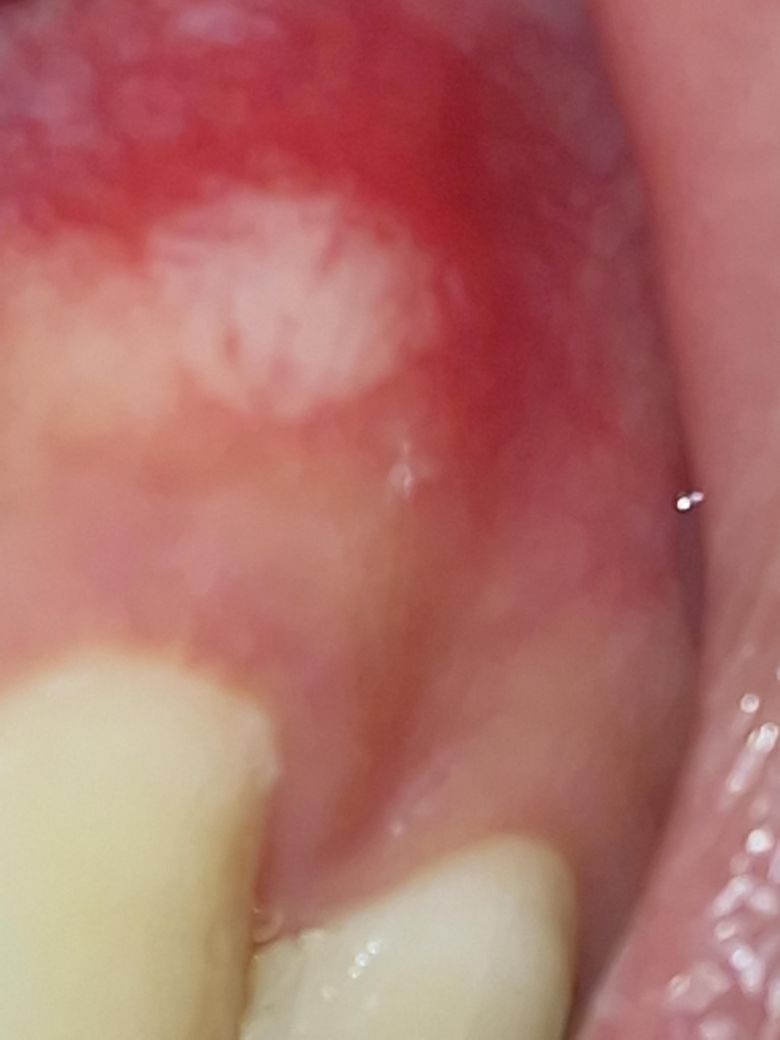

구내염이 2주일간 안사라져요. 구강암인건가요?

며칠전에 치과에서 입 벌리도록 유지시키는 장치? 같은걸 끼다가 송곳니쪽 잇몸에 자극이 가해져서 구내염이 생겼는데, 2주가 지났는데도 형태가 그대로에요.

만지면 다른 부분보다 살짝 민감한 것 이외에는 먹을때나 닿을때 통증같은건 없는데 그냥 아무는 단계인가요?

단순 구내염의 양상은 아닙니다. 다만, 악성 병소의 양상도 아니니 너무 걱정 마시고 구강내과 한번 가보시기 바랍니다.